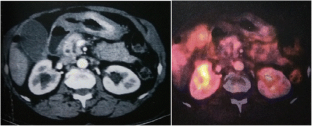

Fig. 1